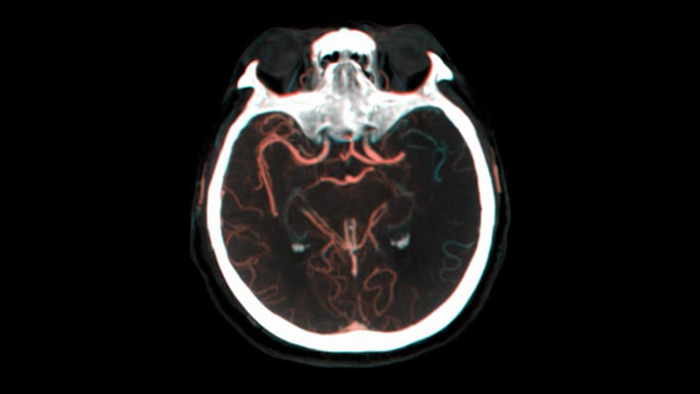

Verifizierung des Behandlungserfolgs

DSA Visualisierung

Hochwertige DSA-Visualisierungen ermöglichen es Ihnen, zu beurteilen, ob das Gerinnsel vollständig entfernt wurde und ob sich Teile davon distal in das Gehirn verteilt haben. Sie können die Wiederherstellung des Blutflusses zur Penumbra verifizieren und eine Überprüfung auf periprozedurale Blutungen vornehmen.